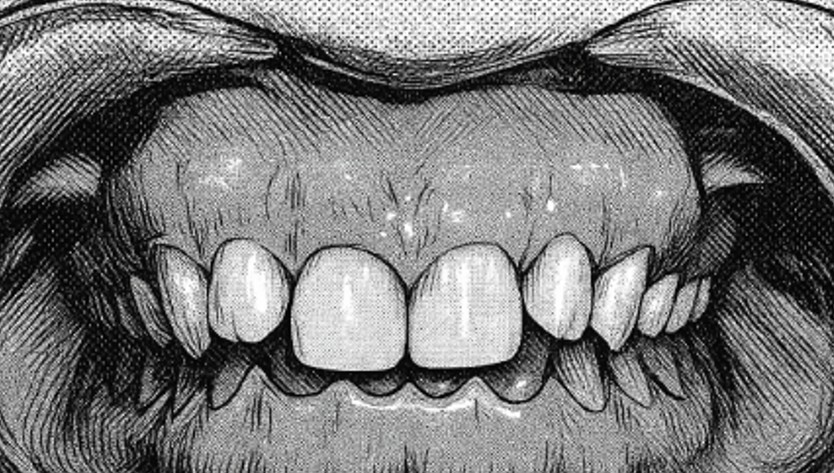

不正咬合の種類:下顎前突

下顎前突

※”受け口“の状態をいいます。

ただ単に下の歯(顎)が出ている場合と骨格的な場合があります。

遺伝的なこともありますが、小児期の癖(指しゃぶり)にも影響されます。